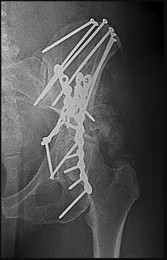

Explanation:

Day Type II crescent fractures involve a major fracture line exiting the iliac wing, but a substantial portion of the posterior ilium remains attached to the sacrum via the posterior SI ligaments. Biomechanical studies have demonstrated that for Day Type II fractures (where the fracture extends into the SI joint), combining an iliosacral screw to stabilize the SI joint component with an orthopedic plate for the iliac wing fracture provides the most stable construct, superior to either method alone.